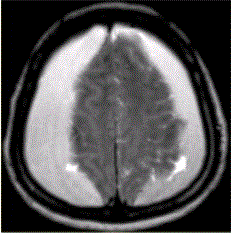

问题 男性,55岁。突发昏迷,MRI表现如下图,可能的诊断是

选项 A.硬膜下血肿 B.正常 C.硬膜外血肿 D.脑挫裂伤 E.脑脓肿

答案 A